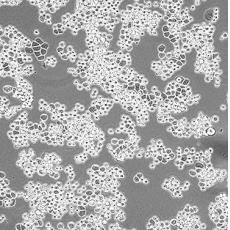

MDA-MB-453

產(chǎn)品名稱 MDA-MB-453

中文名稱 人乳腺癌細(xì)胞

組織來源 乳腺腺癌;胸腔積液轉(zhuǎn)移;女性

生長特性 adherent

形態(tài)特征 epithelial

細(xì)胞描述 該細(xì)胞系由CailleauR在1976年從一名48歲的患有轉(zhuǎn)移性乳腺癌的白人女性的心包滲出液中分離建立的。該細(xì)胞表達(dá)FGF的受體。